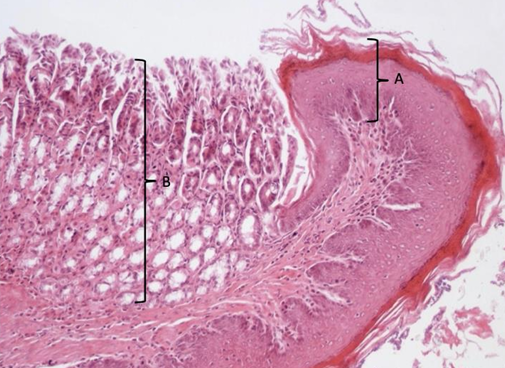

nabłonek wielowarstwowy płaski

gruczoły wpustowe - nabłonek jednowarstwowy walcowaty

wpust żołądka 402a

żołądek

błona śluzowa z gruczołami żołądkowymi i okładzinowymi i kubkowymi

mięśniówka

nabłonek wielowarstwowy płaski od środka

blaszka właściwa (mięśniowa błony śluzowej) = tkanka łączna

mięśniówka okrężna i podłużna

przydanka

przełyk nr 405